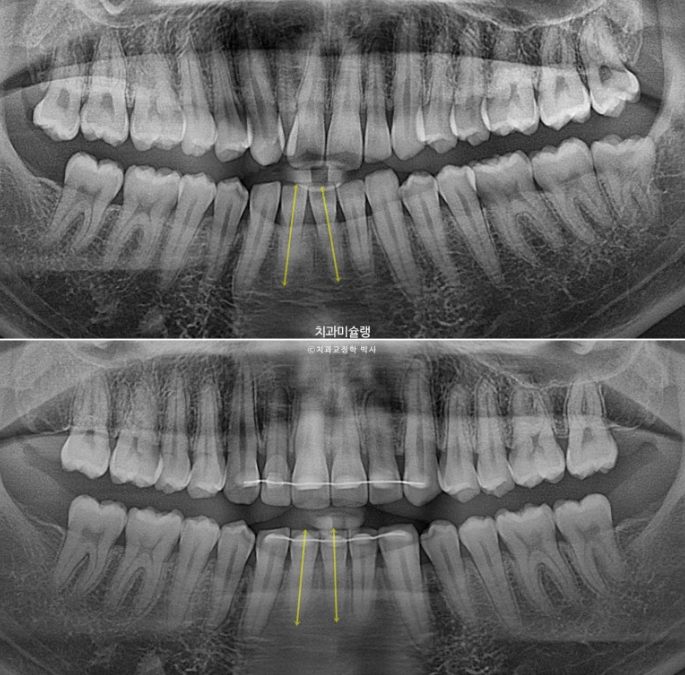

이제 전 후 비교 보겠습니다.

24.03~25.11

어금니 교합은 기존 2급에서 1급 교합관계를 달성

물샐틈 없는 교합은 교정치료의 기본입니다.

왜소치 덧니쪽으로 쏠려있던 앞니 중심선이 비로소 중간으로 맞춰졌습니다.

옥니의 개선으로 미소가 환해졌습니다.

입매변화는 없이 잘 유지가 되었고 위 앞니 각도의 옥니 개선이 눈에 띕니다.